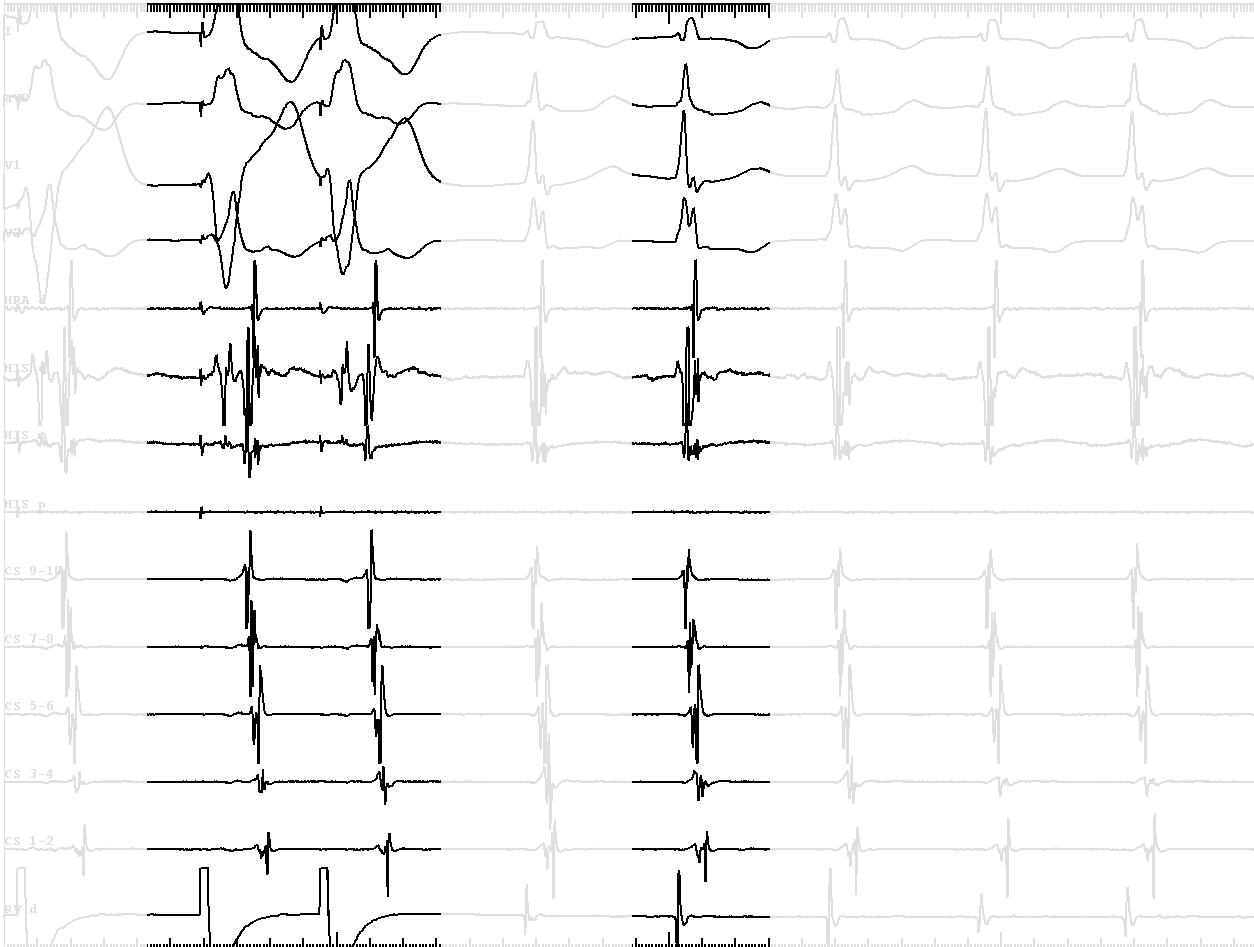

• VA conduction with His after A - bystander His activation, ? AP

• VH block with VA conduction - further confirms bystander His

• Short VA during tachycardia - not AVRT

• Narrow QRS similar to sinus - antegrade conduction through another AV node

• Internodal tachycardia ? - A before His, tachy continues with VH block

• Therefore, AVNRT involving inputs to anterior node

Anterior His

tachy_ant_his.jpg

Anterior His during sinus rhythm

sinus_ant_his.jpg